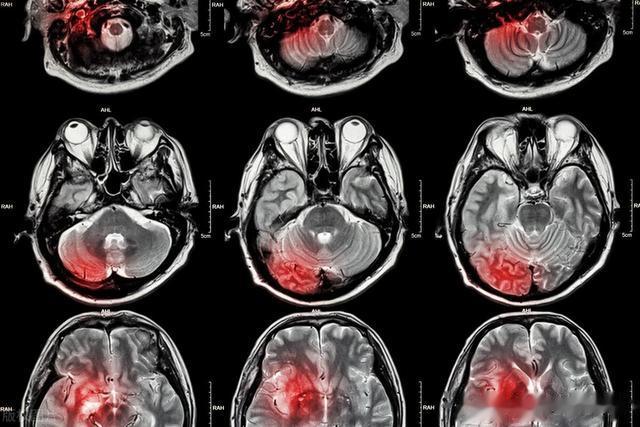

其实,像张阿姨这样的情况并不少见。每年冬天,医院里因为脑出血而住院的人骤增,而其中大部分都有一个共同点:高血压。高血压就像一颗埋在身体里的“定时炸弹”,平时看似无声无息,但一旦引爆,后果不堪设想。而冬季寒冷的天气,更是引发脑出血的“催化剂”。那么,高血压究竟是如何与脑出血扯上关系的?在寒冷的冬季,又该如何保护自己,让这颗“炸弹”始终保持安静?

### 高血压埋下的隐患高血压被称为“沉默的杀手”,是因为它在早期往往没有明显症状,很容易被忽视。然而,它对血管的损伤却是持续且深远的。当血压长期处于较高水平时,血管壁会承受巨大的压力,逐渐变得脆弱,失去弹性,甚至出现微小的破裂。这种情况下,血管就像一根老化的水管,随时可能因为压力过大而爆裂。

脑出血,顾名思义,就是大脑内的血管破裂导致出血。冬季的寒冷更是加剧了这一风险。寒冷会让血管收缩,血液流动变得不畅,血压也随之升高。对于患有高血压的人来说,这种环境无疑是雪上加霜。一旦血压突然升高,脆弱的血管很可能承受不住压力而破裂,导致脑出血的发生。